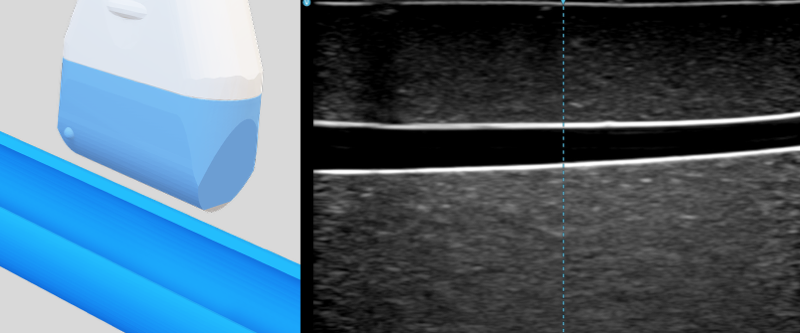

- Long axis (longitudinal) view: The probe is parallel to the travelling direction of the vessel. The vessel appears as a long pipe. It enables full visualization of the needle shaft and tip, but requires precise alignment with the vessel and needle.

Two compressible veins and one incompressible artery were shown in this clip.